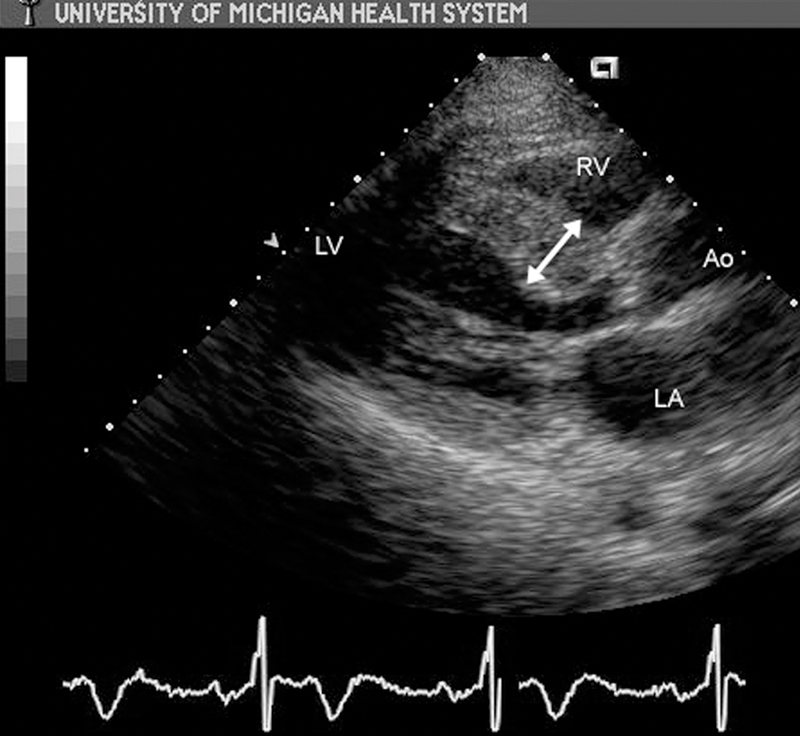

فحوصات تشخيصية لبعض امراض القلب والشرايين التاجية